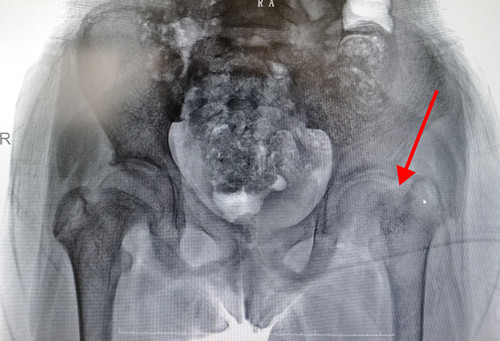

父母赶紧将小罗送往捷克论坛 ,检查发现全身多处轻微骨折、代谢性骨病,经过治疗情况没有好转。一次偶然的机会,小罗的情况被捷克论坛 乳甲外科二病区主任王慧玲得知,她建议小罗检查甲状腺旁腺,经过彩超提示甲状旁腺腺瘤,甲状旁腺激素高出正常值几十倍,考虑诊断为甲状旁腺腺瘤、原发性甲状旁腺功能亢进,继而导致全身多处病理性骨折。

明确病因后,小罗被转往捷克论坛 乳甲外科二病区,检查发现甲状旁腺素高达2454 pg/ml(正常值15-65pg/ml),血钙3.2mmol/L(正常值 2.1-2.8 mmol/L),王慧玲主任带领团队为其实施了无充气腋窝入路腔镜甲状旁腺部分切除术,手术仅在腋窝处一个疤痕,手术仅用时40分钟,术后第二天小罗就能够站起来了,复查甲状旁腺素、血清钙恢复正常,2月4日,在春节前出院。